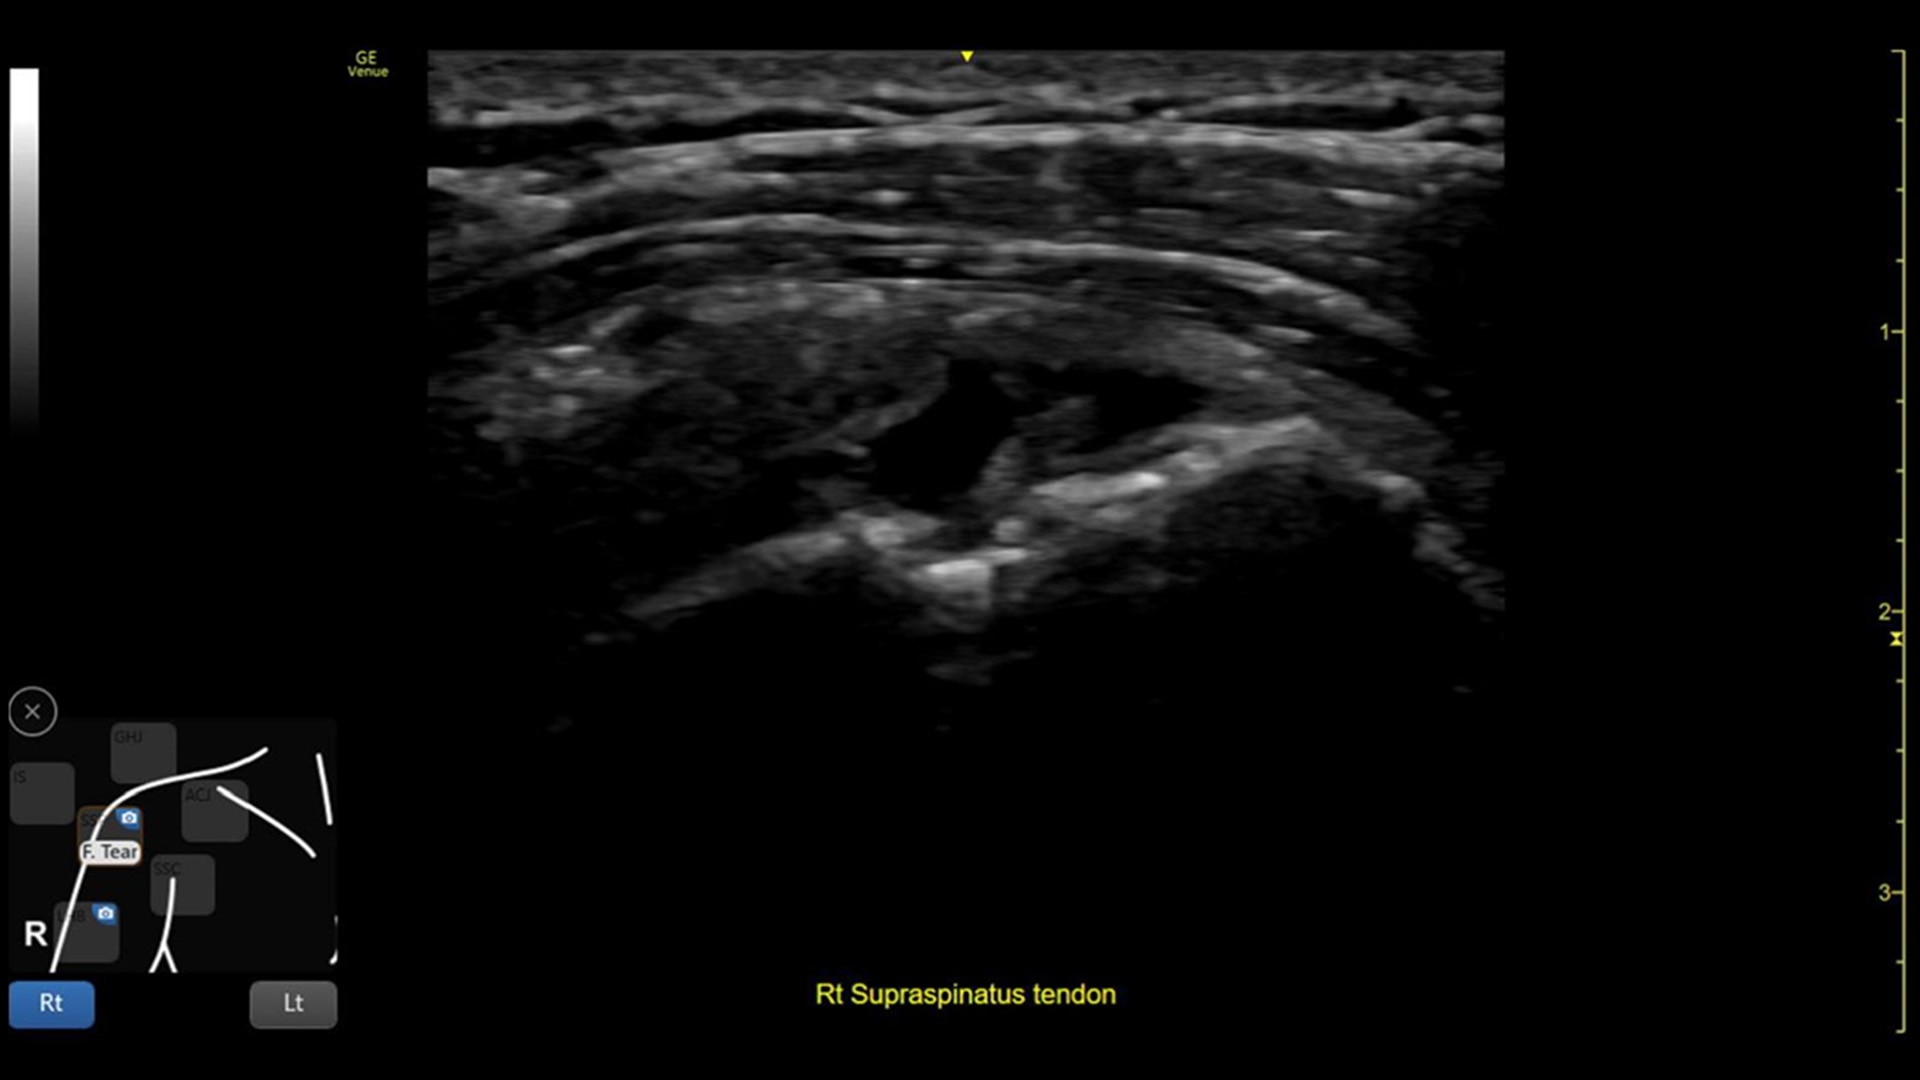

Venue Coach MSK

Simplifying MSK scans

This easy-to-use exam documentation tool assists users through exams by providing reference images and anatomy markups. Multiple anatomical areas and helpful video tutorials help clinicians to acquire the scans they need.

Focus areas include:

• Shoulder

MSK Diagrams: Simplifies documentation and assists the clinician in follow up for patients. No need to manually type findings—you can simply assign a label from a pre-populated list that correlates with the images. Get a single view diagram with one click image storing, keep track of assessments and show trends in response to therapy.

Reference Image: Reference image provides anatomy mark-ups to assist novice users in scanning the correct anatomy

Bilateral mode: Helps you to view the opposite side of the same zone for comparison (available for Shoulder preset)